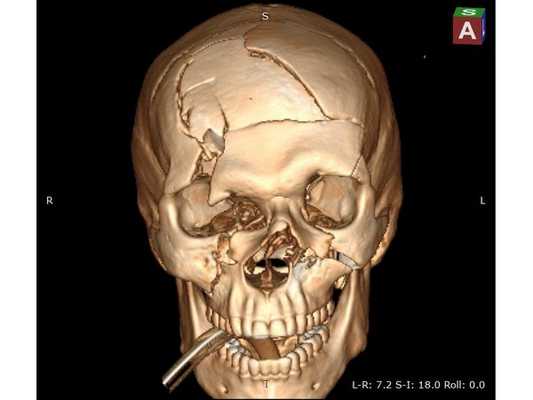

КТ головного мозга: оскольчатый вдавленный перелом лобной кости, линейный перелом ската затылочной кости, а также перелом лицевого отдела черепа III степени по Le Fort с остаточной деформацией стенок; множественные ушибы и отёк вещества головного мозга лобных долей; скопление крови в пазухах носа. КТ шейного и поясничного отделов позвоночника: травм и патологий нет. КТ грудной клетки и грудного отдела позвоночника: ушиб правого лёгкого. Офтальмологический осмотр: контузия правого глазного яблока тяжёлой степени, скопление крови между сетчаткой и пигментным эпителием левого глаза.

Сочетанная черепно-челюстно-лицевая травма. Открытая проникающая черепно-мозговая травма. Ушиб головного мозга тяжёлой степени с преимущественным поражением лобных долей и формированием очагов размозжения в полюсно-базальных отделах. Многооскольчатый вдавленный перелом лобной кости, переходящий на основание черепа. Перелом лицевого отдела черепа III степени по Le Fort с деформацией стенок правой глазницы. Ушиб правого глаза тяжёлой степени, субретинальное кровоизлияние левого глаза.

Необходимо выполнить трепанацию черепа в лобной области; удалить, сопоставить и зафиксировать вдавленные костные фрагменты при помощи минипластин; удалить внутримозговую гематому; восстановить форму свода черепа с использованием металлической пластины. Ход операции: ⠀•⠀выполнен разрез мягких тканей в лобной области по Зуттеру, гемостаз моно- и биполярной коагуляцией по ходу скелетирования кости до уровня надбровных дуг, кожно-апоневротический лоскут откинут базально; ⠀•⠀открыт доступ к вдавленным костным фрагментам, в правой надглазничной области имеется повреждение костных фрагментов твёрдой мозговой оболочки и головного мозга, виден мозговой детрит (размозжённая мозговая ткань); ⠀•⠀с помощью краниотома костные фрагменты мобилизованы и удалены из раны, визуализировано повреждение твёрдой мозговой оболочки в области правой лобной доли; ⠀•⠀плотные сгустки крови и мозговой детрит аспирированы, отмыты физраствором и удалены, объём мозгового детрита — примерно 30 мл; ⠀•⠀произведён гемостаз с использованием биполярной электрокоагуляции, перекиси водорода и воска, твёрдая мозговая оболочка ушита и подшита по периметру костного дефекта нитью Викрил; ⠀•⠀самый крупный фрагмент кости уложен на место, костный дефект закрыт металлической пластиной; ⠀•⠀все костные фрагменты и сетчатая пластина фиксированы 10 винтами 1,5*5,0 мм и 2 минипластинами, операционная рана ушита послойно, кожа ушита непрерывным швом по Мультановскому, наложена асептическая повязка.